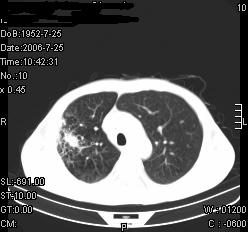

患者,男,54岁,咳嗦,咳痰20天。抗炎治疗2周。现esr76mm/h,目前患者症状明显好转,但发现两次ct片未见明显变化。两次分别做与7.25、7.31。第一次诊断右肺上叶炎症累计胸膜。大家看,从影像上内排除结核吗?

结核的可能性非常大,右上肺病变应该考虑干酪性肺炎。理由:

1.纵隔内多发淋巴结肿大。

2.esr76mm/h。

3.虽经抗炎治疗肺窗病灶有所吸收、减小,但纵隔窗病灶形态、密度、范围无明显变化。如果是单纯的大叶性肺炎,“抗炎治疗2周,目前患者症状明显好转”病灶应该基本消散了,至少也处于吸收消散期,密度变淡、范围变小。同时本病例所示其内的密度不均匀,见多发大小不一空洞样影也不符合大叶性肺炎吸收消散期表现。

病灶特点:片状 索条 结节混杂影,部分融合,密度不均,广泛累及相应胸膜.

临床治疗;二周未吸收.但症状好转.

多考虑:肺结核.